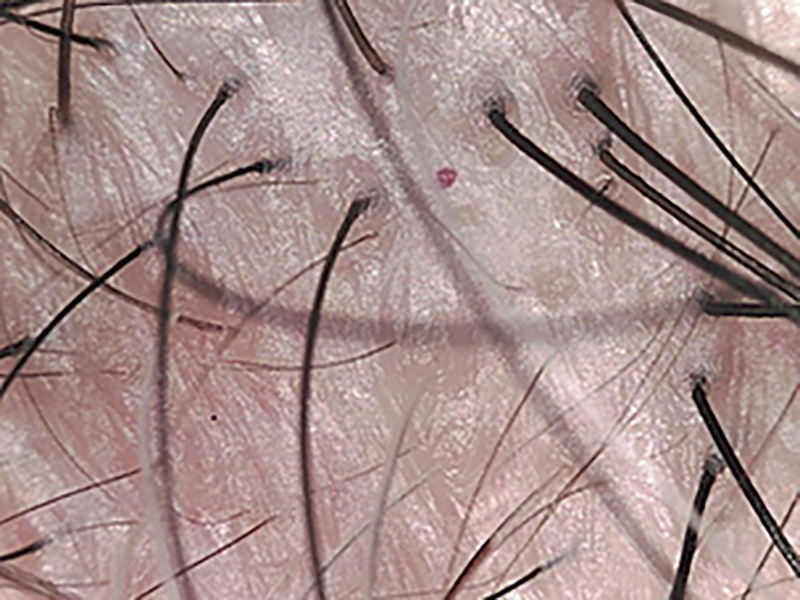

【3】クリニックではマイクロスコープで頭皮の状態が確認できる

「自己診断では、薄毛の進行具合までは判断しにくいもの。クリニックでは、マイクロスコープを使って頭皮の状態や毛穴の皮脂汚れ、毛髪の太さなどを確認することができます」

●健康な頭皮

充分な毛量がある頭皮では、1つの毛穴から太い毛が3本生え、根元も立ち上がっている。

●薄毛が進行した頭皮

薄毛が進行すると、毛の生えていない毛根や細い毛が目立ち、血行不良などが原因で頭皮が黄ぐすんで見える。